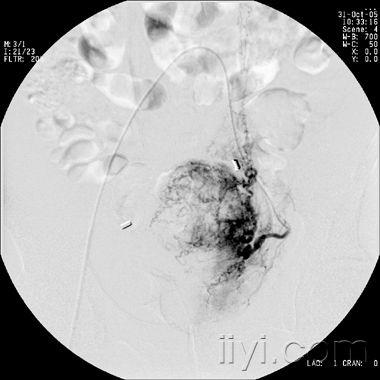

宫颈癌介入治疗图片